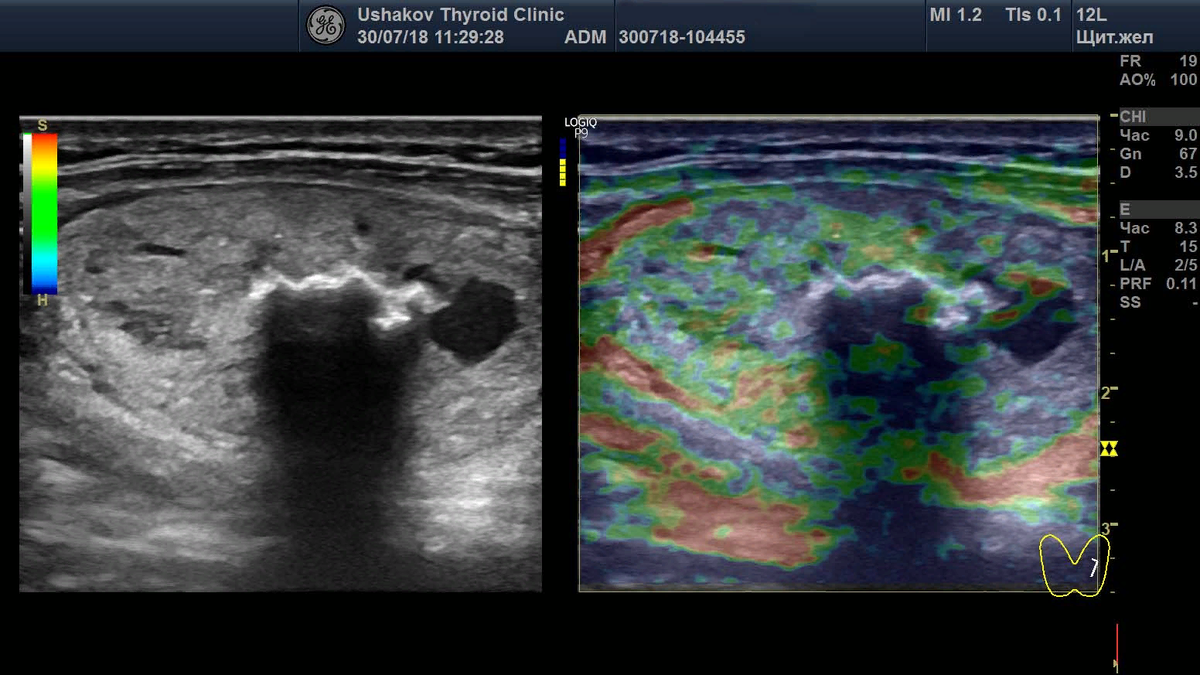

УЗ-снимки (в серой шкале и эластографии).